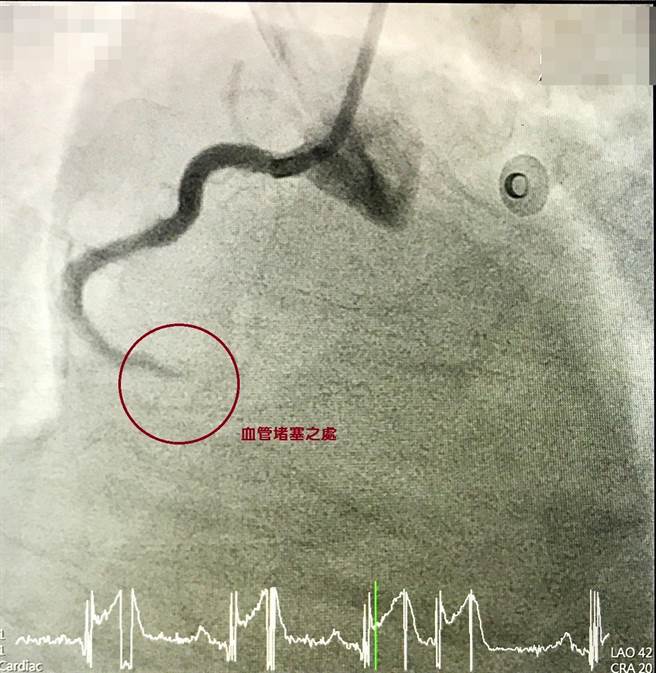

心導管手術前(血管堵塞)。(大甲李綜合提供/陳淑娥台中傳真)